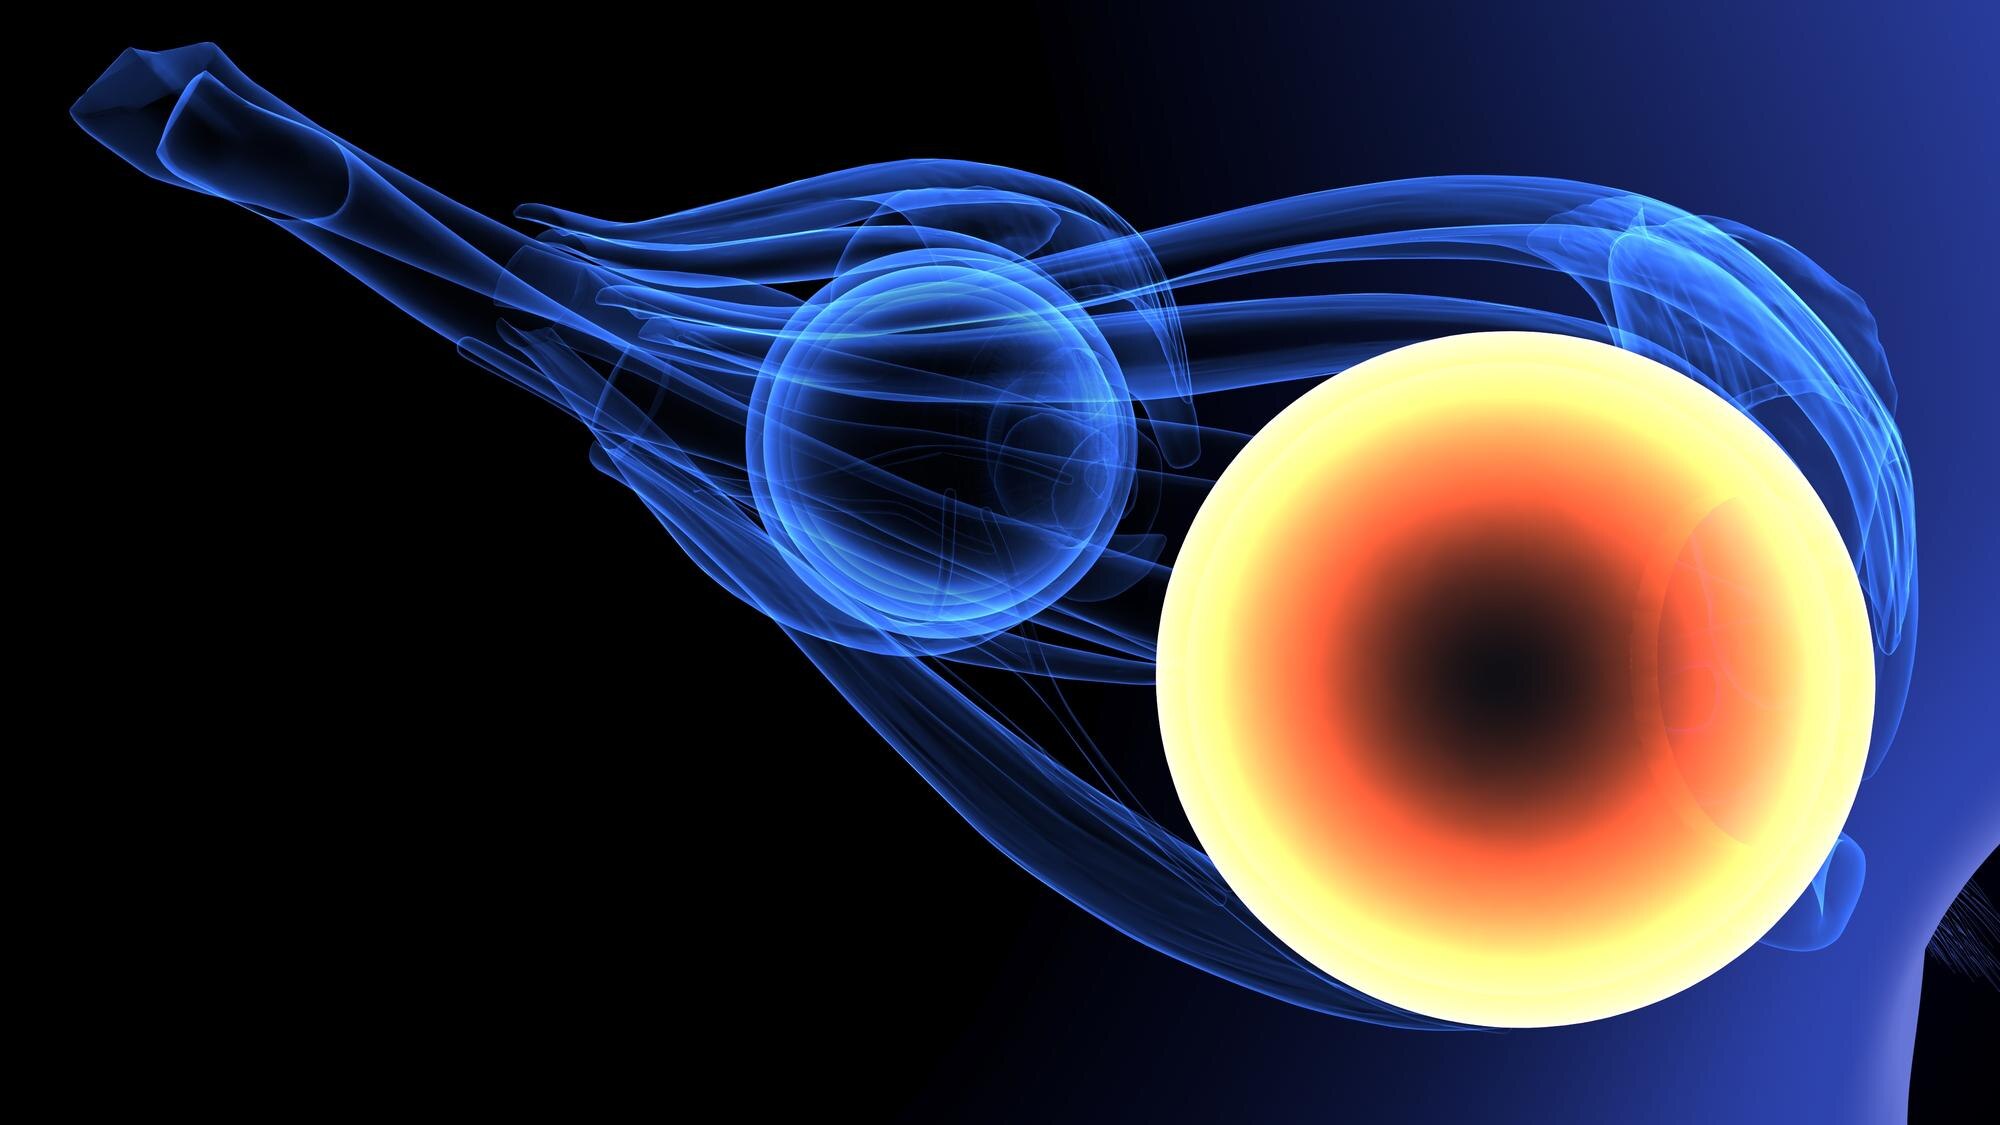

Musculoskeletal ultrasound is a technique that uses sound waves to produce images of muscles, tendons, ligaments, and joints. Unlike other imaging methods, it avoids radiation, making it a safe option for children. This scan provides clear details about the internal structure, helping to identify any concerns. It’s especially useful in examining soft tissues that might not be visible with X-rays. Plus, it’s quick and painless!

For parents, the word “non-invasive” offers comfort. With musculoskeletal ultrasound, there’s no need for needles or sedation. Your child can relax during the process. The scan is performed on the skin surface, using a small device called a transducer. This device sends out sound waves and then listens for the echoes that bounce back. These echoes create the images that doctors use to diagnose and plan treatments, ensuring your child is comfortable throughout.